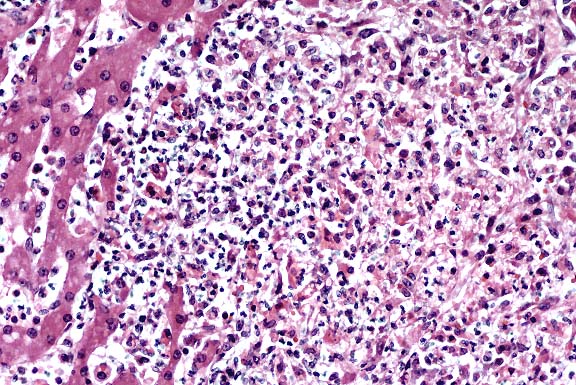

- Contributor's Diagnosis and Comments: Liver, hepatitis,

suppurative, with necrosis, multifocal, coalescing, severe, compatible

with Tyzzer's disease of neonatal foals.

- Intracellular bacteria compatible with Clostridium piliforme

(Bacillus piliformis) were demonstrated in histopathological

sections. Lesions and organisms are compatible with Tyzzer's

- Case 12-2a. Liver. Locally extensive hepatic necrosis

with an influx of neutrophils. 20X

AFIP Diagnoses:

- 1. Liver: Hepatitis, necrotizing, neutrophilic, acute, multifocal

to coalescing, random, severe, Quarter Horse, equine.

- 2. Liver: Cholestasis, canalicular, multifocal, moderate.

- Conference Note: Tyzzer's disease is an acute, highly

fatal, epizootic enterohepatic disease of neonatal or weanling

animals. It has been reported in numerous animal species, including

horses, cattle, mice, rats, hamsters, guinea pigs, rabbits, foxes,

and coyotes. The causative agent, Clostridium piliforme, is a

gram-negative, spore-forming, motile, obligate intracellular

bacterium with peritrichous flagella. The vegetative form causes

the disease state, and appears as bundles or "haystacks"

within its target cells, i.e. enterocytes and hepatocytes. Visualization

of the bacteria in histologic section is enhanced with silver

stains such as the Warthin-Starry procedure.